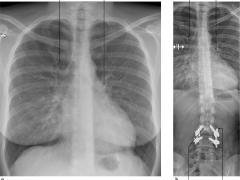

Astma en COPD

Astma